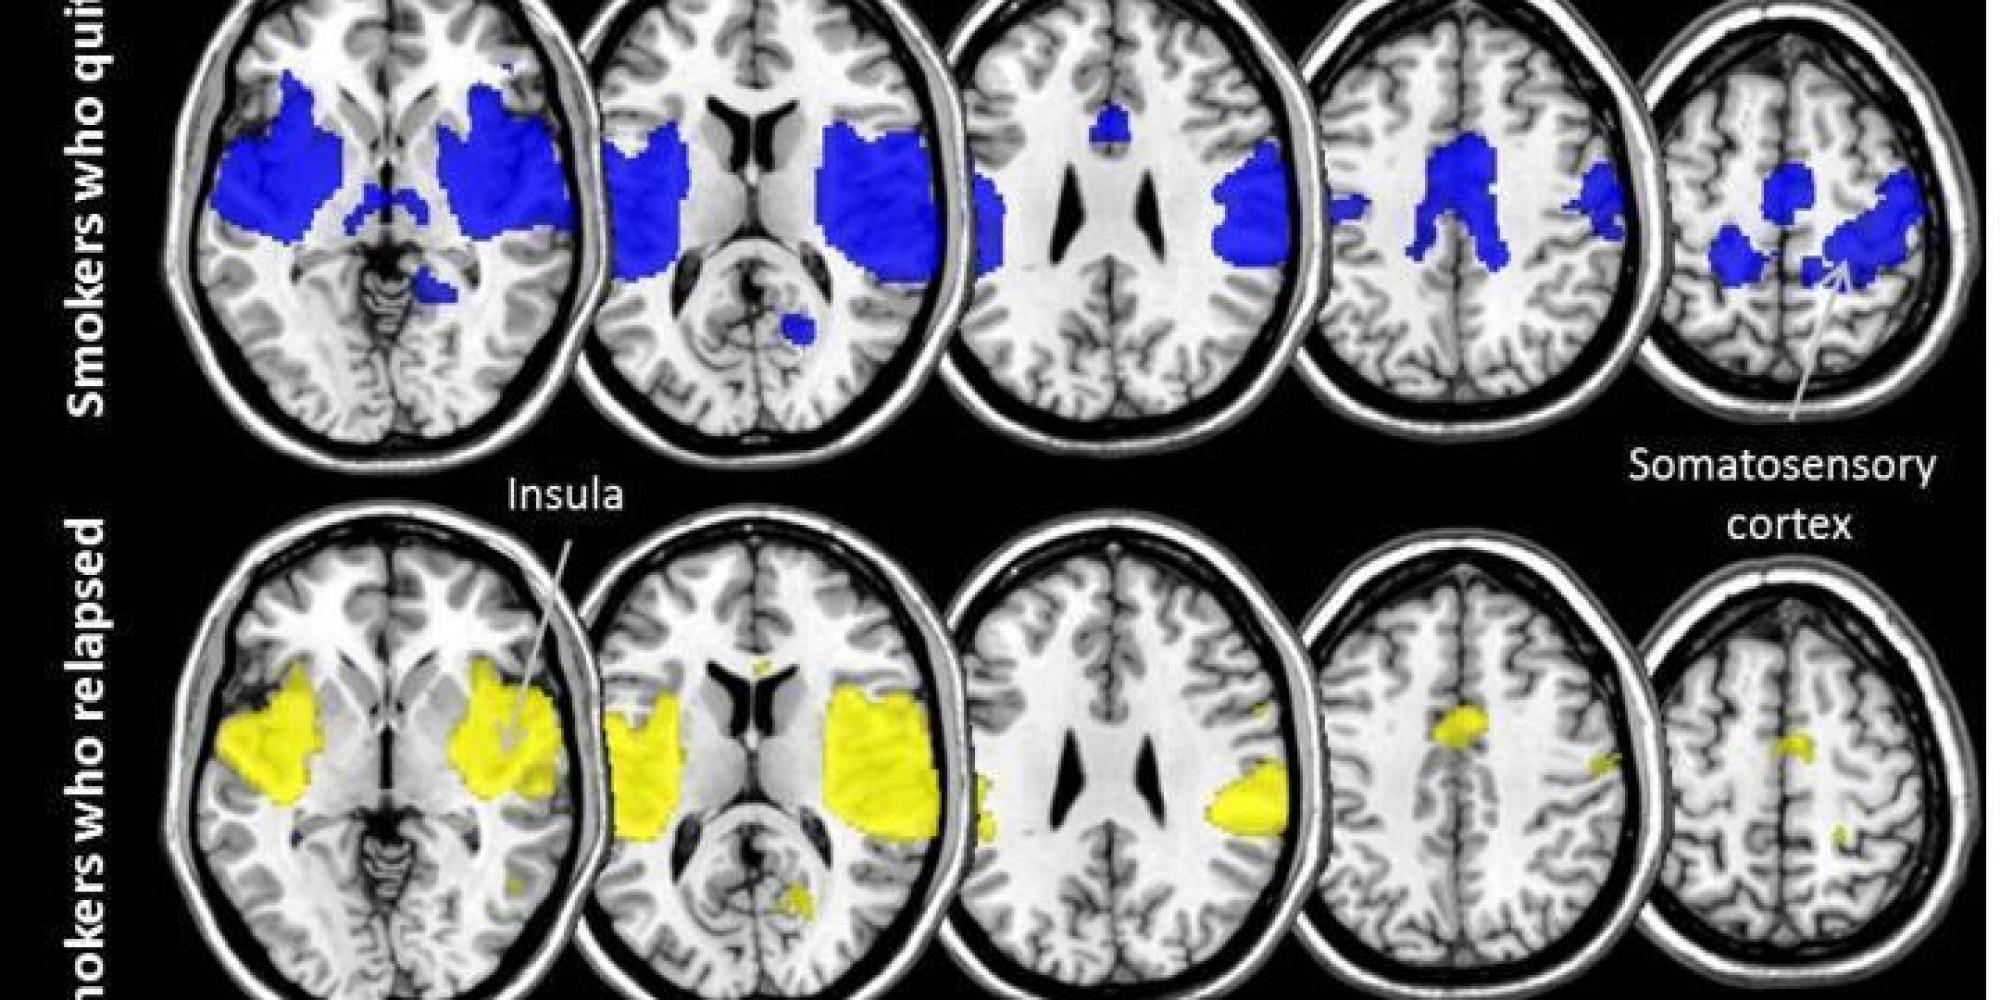

Quitting smoking relies on stronger brain networks CNN Smokers And Nonsmokers Brain Although a substantial body of previous functional magnetic resonance imaging (fmri) studies have revealed different brain. Functional magnetic resonance imaging (fmri) studies of smokers have found increased blood oxygen level dependent (bold). Although differences could have been related to the effects of nicotine on smokers’ brain function, we compared nonsmokers’. Smokers showed lower rsfc within the dorsal attention network (dan). Smokers And Nonsmokers Brain.

What Studying The Brains Of Smokers Reveals About Quitting Successfully Smokers And Nonsmokers Brain Although a substantial body of previous functional magnetic resonance imaging (fmri) studies have revealed different brain. Although differences could have been related to the effects of nicotine on smokers’ brain function, we compared nonsmokers’. Smokers showed lower rsfc within the dorsal attention network (dan) in the left superior and middle frontal gyrus and left. Specifically, we performed a conjunction analysis. Smokers And Nonsmokers Brain.